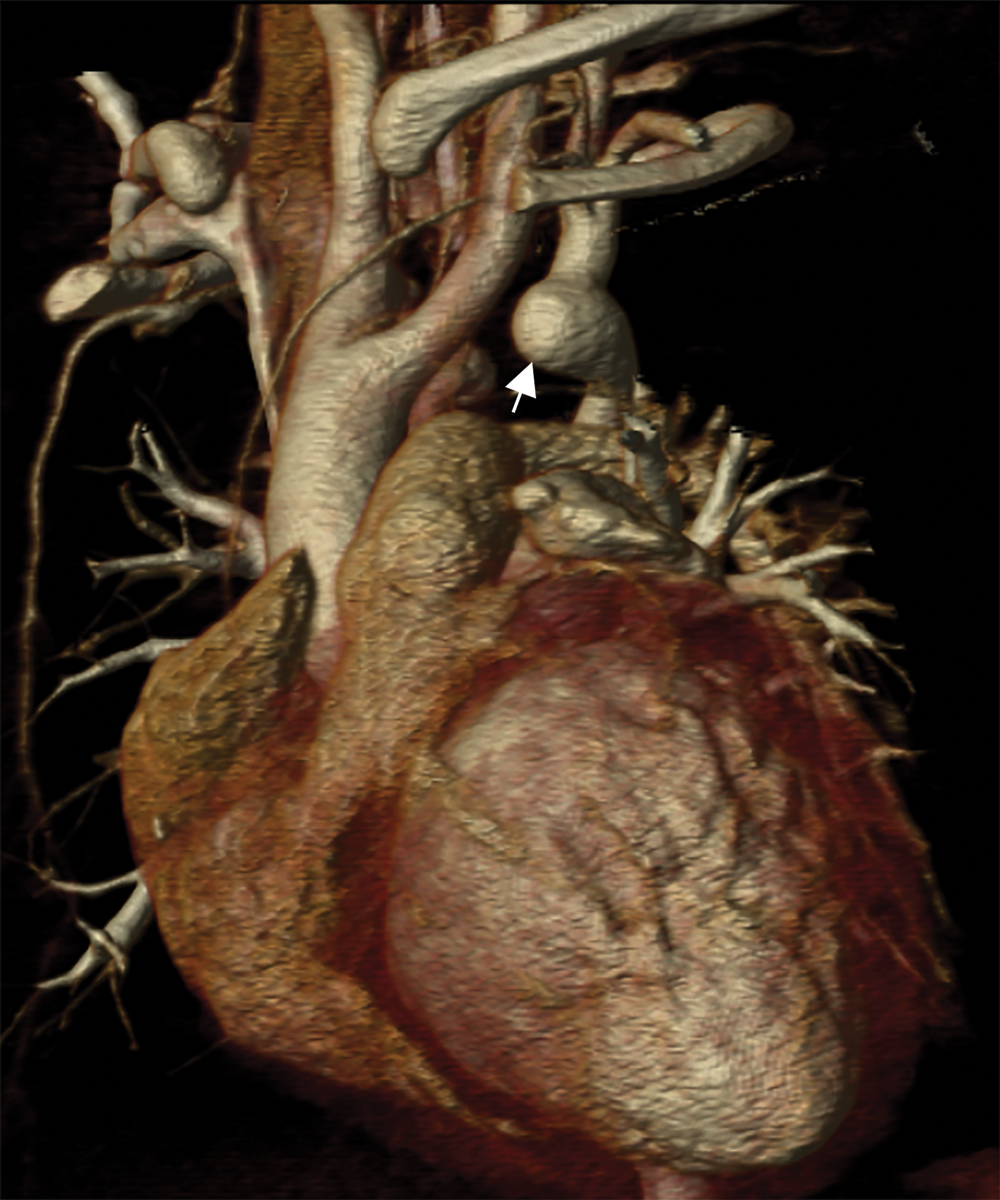

Cardiac CT (Figs. 2–4) identified an ascending aorta that gave rise to dilated common carotid arteries and an extremely tortuous and stenotic right aortic arch. The right subclavian artery originated beyond the area of severe arch stenosis with an additional area of narrowing at its origin. Collateral vessels were seen in the right side of the neck. A long and relatively narrow right-sided dorsal aortic root passed in a caudal direction where it was joined by an equally long but larger left-sided dorsal aortic root reflecting ductal flow in utero. The dorsal roots fused below the level of the carina. The descending aorta was also right-sided but crossed to the left at the level of the diaphragm. The left-sided dorsal root remnant supplied an aberrant left subclavian artery, a dilated left vertebral artery, and collateral vessels in the left side of the neck. There was no evidence of a double aortic arch.

Figure 4: An oblique coronal 3D reconstruction viewed from anterior. The ascending aorta gives rise to the two dilated common carotid arteries. A large ductal remnant is present (arrow). The left subclavian is being supplied by the left-sided dorsal root remnant